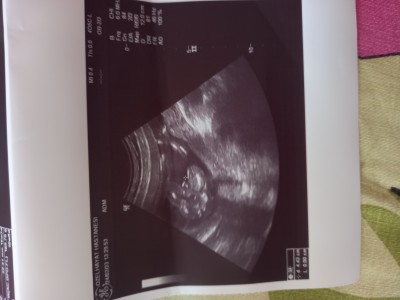

Kizlar 16 haftadan sonra cinsiyeti degisirmi yüzde 90 dedi ?

Canım bu erkek bebis organı. Belli oluyor o kordon degilse ultrasonda sana gösterdiyse gördüysen değişmez...ki o zaman  bacak arası fotosu bide pozisyon net gibi